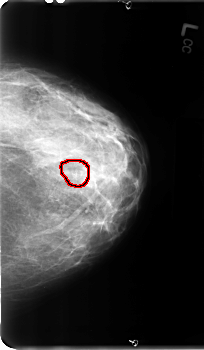

B_3111_1.LEFT_CC

LEFT_CC LINES 4888 PIXELS_PER_LINE 2856 BITS_PER_PIXEL 12 RESOLUTION 50 OVERLAY

FILE: B_3111_1.LEFT_CC.OVERLAY

TOTAL_ABNORMALITIES 1

ABNORMALITY 1

LESION_TYPE CALCIFICATION TYPE PLEOMORPHIC DISTRIBUTION CLUSTERED

ASSESSMENT 4

SUBTLETY 3

PATHOLOGY BENIGN

TOTAL_OUTLINES 1

BOUNDARY